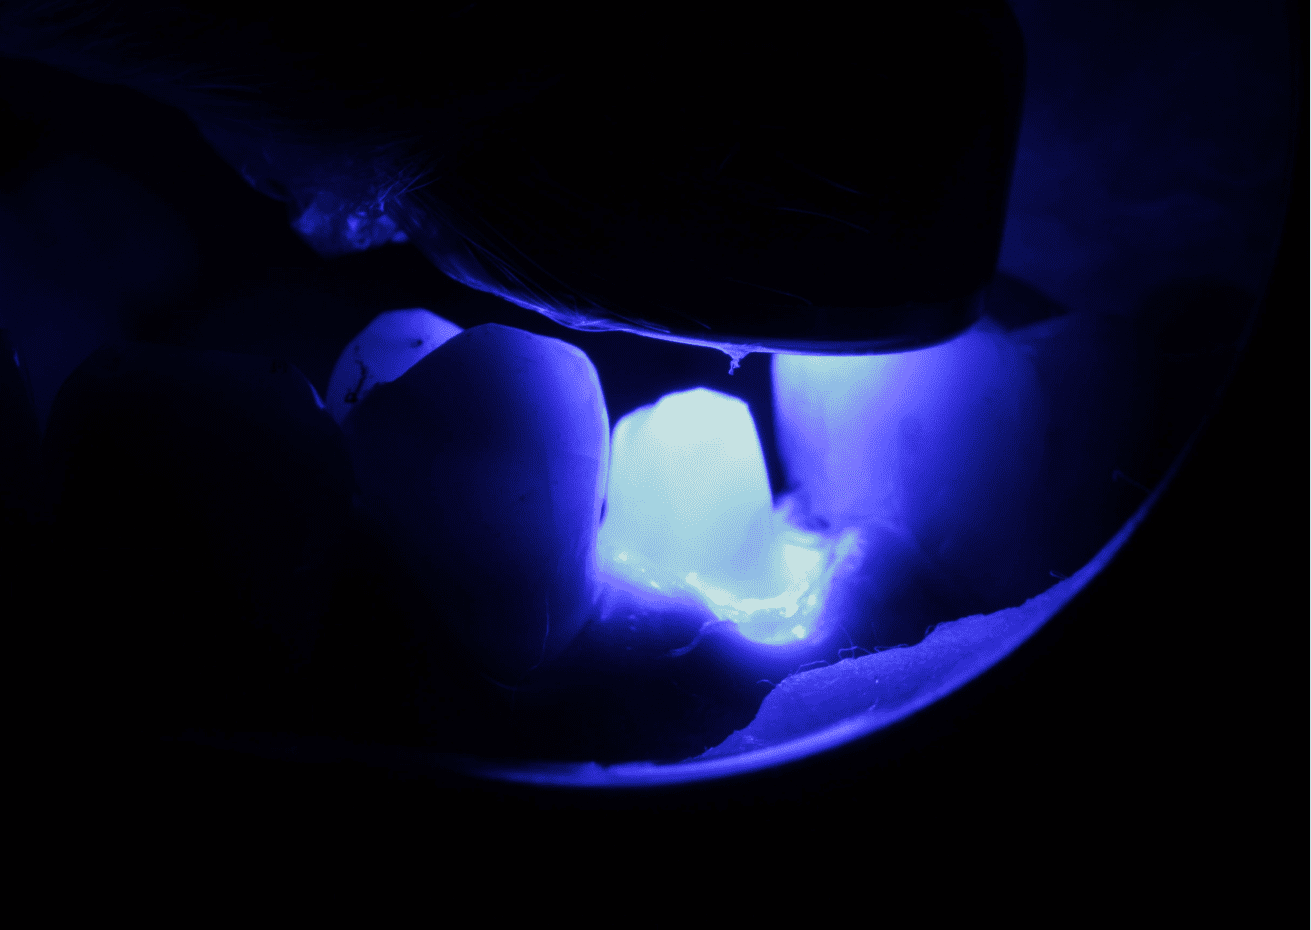

No planejamento reabilitador, foi reabilitado com dois pinos Whitepost SYSTEM cimentados com a combinação de sistema adesivo Ambar Universal APS e cimento resinoso dual Allcem CORE, que também foi utilizado para construção do núcleo de preenchimento.